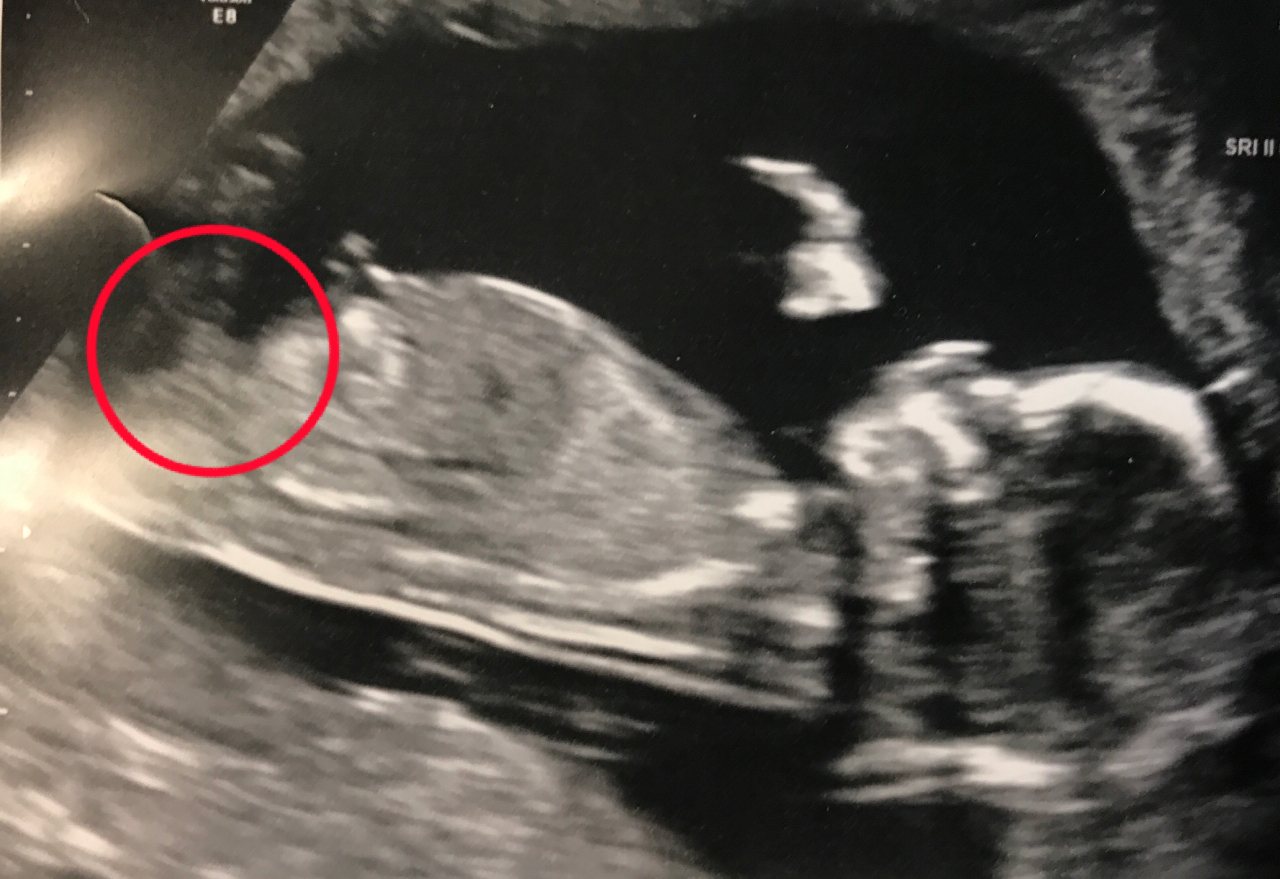

That is the only pic I got. :( I don't know very much about nubs but was guessing it was this part (see circled). Can you tell if that is a nub?Attachment 36512

Yes, that is the nub.

I am leaning boy.

Girl lean

Thanks for your guesses! I'd love any other input too - I think maybe it is a tricky nub? Or perhaps just not the best nub shot. Other symptoms for me have been rough go with morning sickness, acne on arms/back/cheeks/jawline, and hyper mobility in my joints.